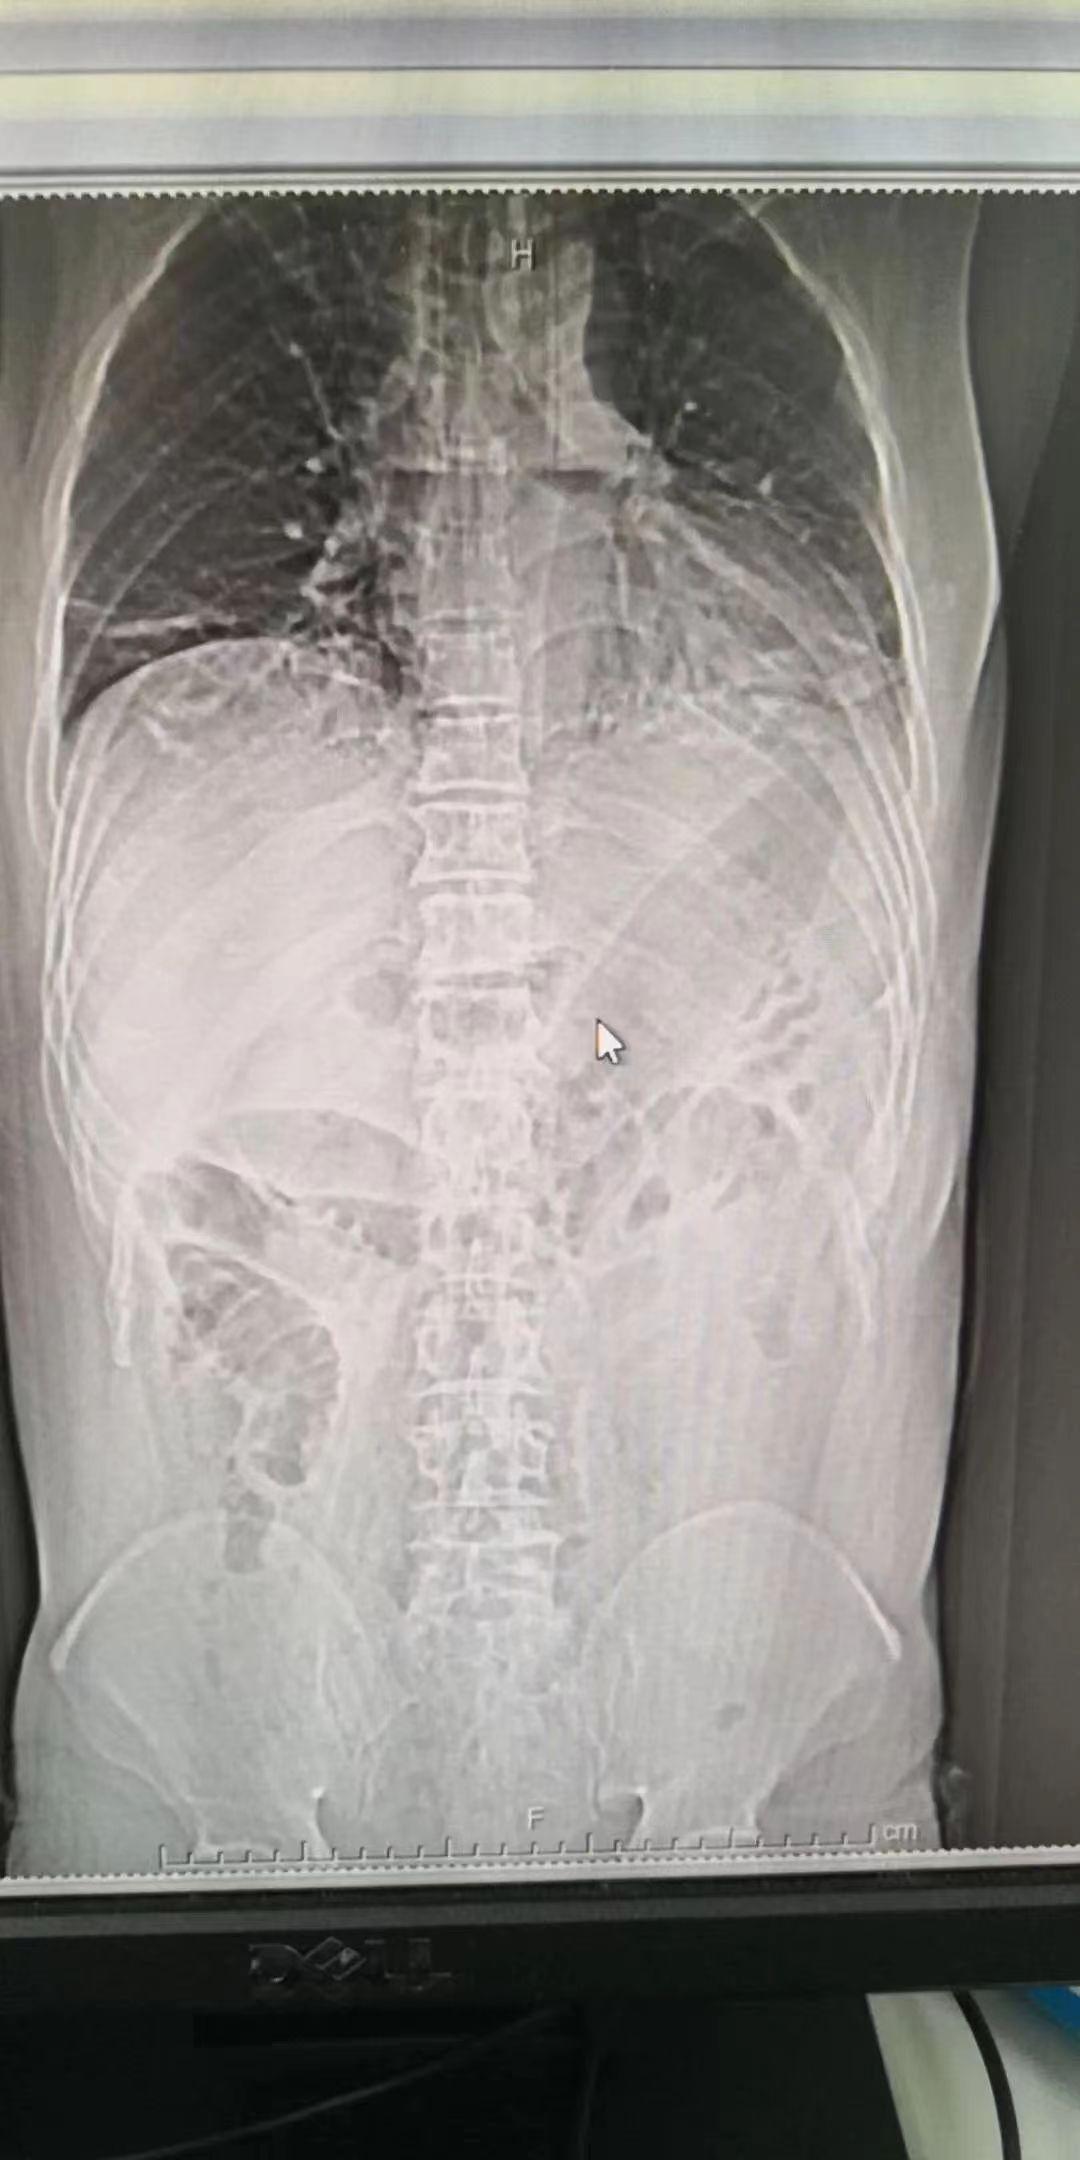

下图就是该患者检查的片子,大家可以一起来找一找茄子在那里:

(图片:茄子位置)

由于茄子太大了,已经顶到了膈肌,马上就要顶到肺和心脏了,同时茄子头顶破了肠道,划了一个口子,所以肚子里的“”也都漏的满肚子都是。